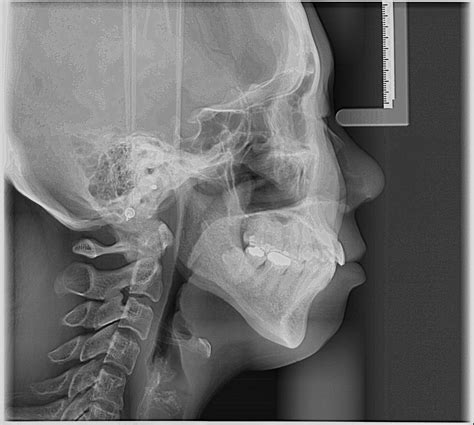

Orthodontic treatment has evolved significantly over the years, with advancements in technology playing a crucial role in improving diagnostic accuracy and treatment outcomes. One of the most essential tools in this field is the Cephalometric X Ray. This imaging technique provides a comprehensive view of the skull and facial bones, enabling orthodontists to plan and execute treatments with precision. This blog post delves into the importance of Cephalometric X Rays, their applications, and the detailed process involved in obtaining and interpreting these images.

A Cephalometric X Ray is a specialized type of radiograph used to analyze the relationship between the teeth and the jaw. It provides a two-dimensional view of the skull, focusing on the facial bones and teeth. This imaging technique is invaluable for diagnosing and treating various orthodontic conditions, including malocclusions, jaw discrepancies, and facial asymmetries.

Interpreting a Cephalometric X Ray requires a thorough understanding of craniofacial anatomy and orthodontic principles. The orthodontist analyzes various landmarks and measurements to assess the patient’s dental and skeletal relationships. Some of the key landmarks and measurements include:

Key Landmarks

The following table outlines some of the key landmarks used in Cephalometric X Ray analysis:

Landmark Description

Sella (S) The center of the sella turcica, a depression in the sphenoid bone

Nasion (N) The most anterior point of the frontal bone at the nasofrontal suture

Orbitale (Or) The lowest point on the inferior margin of the orbit

Pogonion (Pog) The most anterior point on the chin

Gnathion (Gn) The most inferior point on the symphysis menti